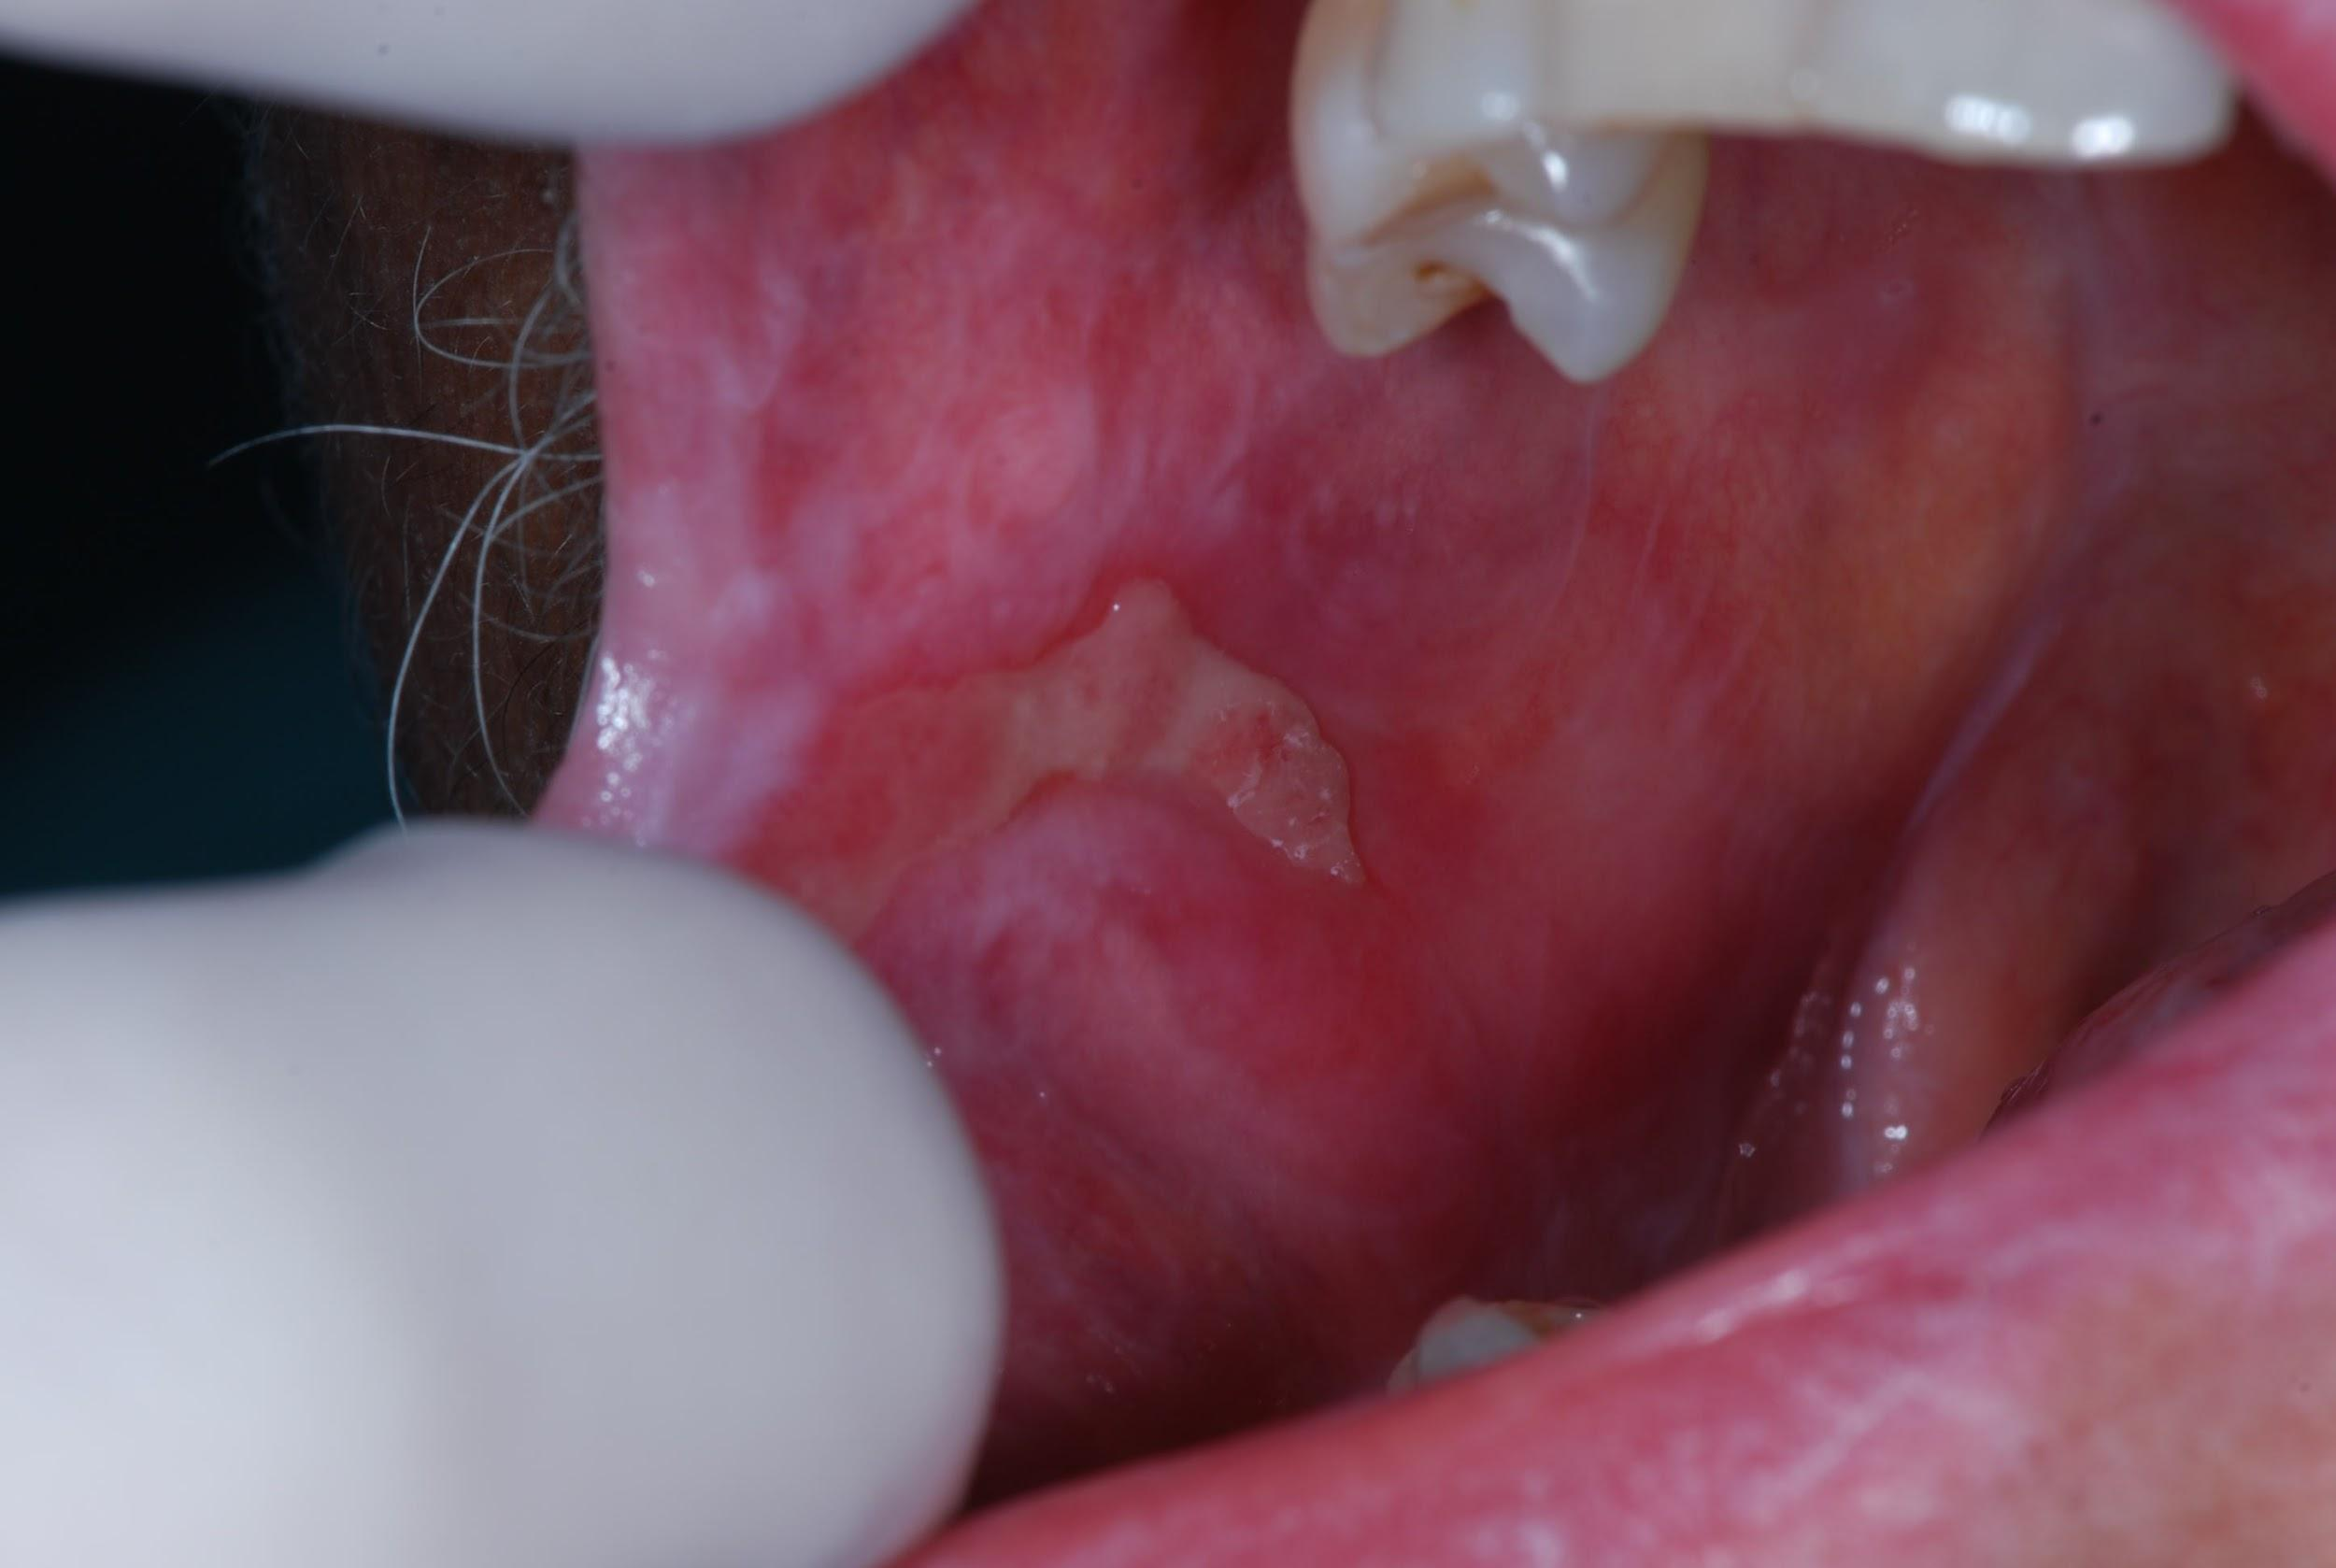

Dental care before HSCT should be performed on all patients to minimize the complications during treatment,46 according to Table 5. During the HSCT, acute oral toxicities62 (infections, OM,63,64 xerostomia63 and acute graft versus host disease (aGVHD))65,66 must be controlled (Table 3) and emergency procedures performed,51 always considering laboratory exams (Table 5). Figure 4 illustrates one of the possible clinical presentations of aGVHD.

Figure 4 Oral manifestation of aGVHD.